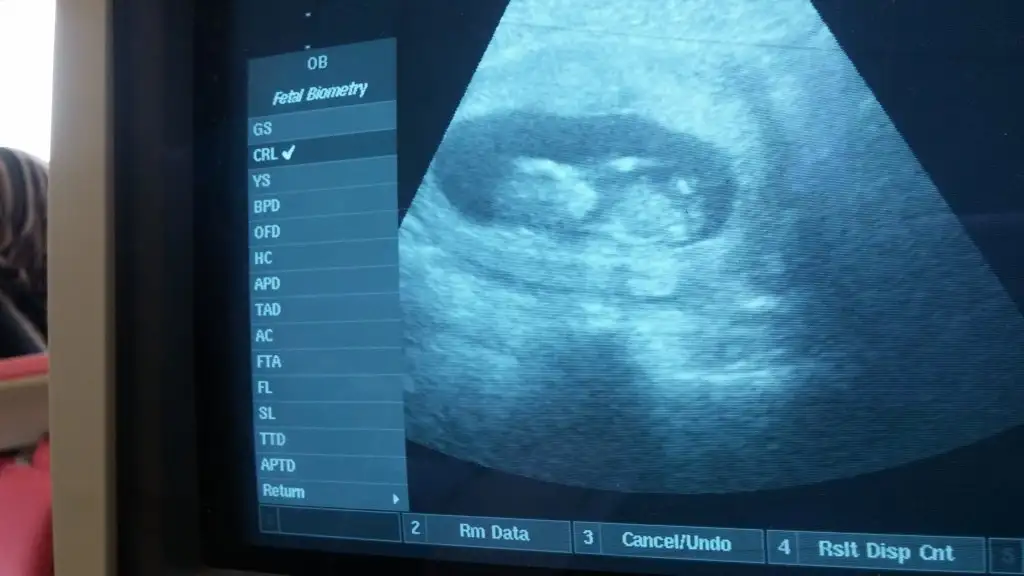

çok belli olmasa da erkek diyorum acılı bi cıkıntı var sanki

bu da kız gibi ama tam belli değil. kız gibi görünen erkeğe dönen nublar var paralel ama uzun ona da benziyo sanki yine de kız dicem bakalım tutcak mı öğrenince yazarsınız12+3 günlük teyzeleri,cinsiyet tahmini bizede yaparmısınız???Eki Görüntüle 1545346

bu da kız gibi ama tam belli değil. kız gibi görünen erkeğe dönen nublar var paralel ama uzun ona da benziyo sanki yine de kız dicem bakalım tutcak mı öğrenince yazarsınız